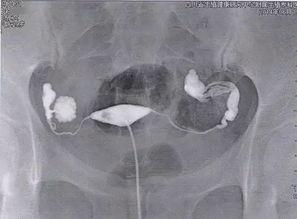

3. X光拍摄

在造影剂注入后,医生会使用X光设备拍摄你的腹部,以便观察输卵管是否通畅。这时,你可能会感到有点胀痛,但这是正常的生理反应。

4. 观察结果

拍摄完成后,医生会根据X光片的结果来判断你的输卵管是否通畅。如果输卵管通畅,造影剂会顺利通过;如果输卵管不通,造影剂可能会在某个地方停滞。